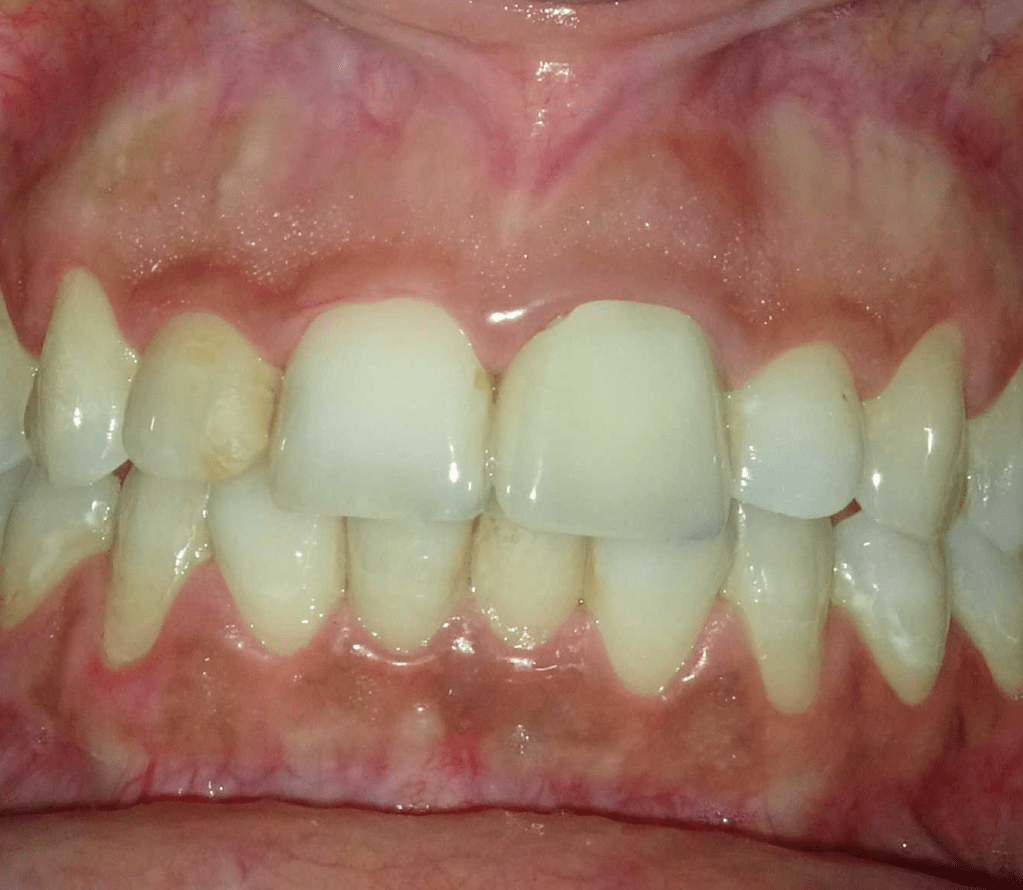

Incisivo superior Endo-perio

Incisivo superior trauma